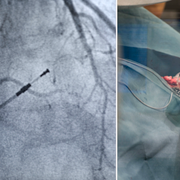

Granskningen av implantat